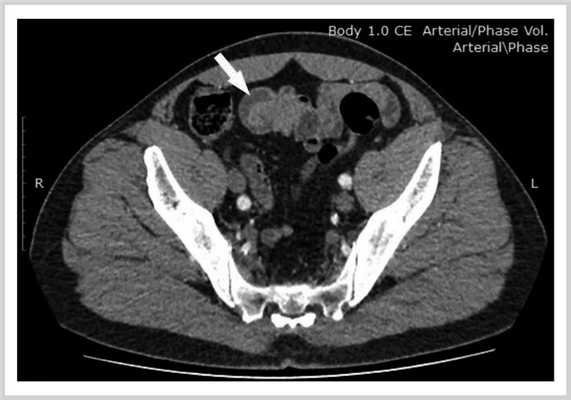

Диагностирован хронический атрофический гастрит, ассоциированный с Helicobacter pylori. Антитела к фактору Кастла, антитела к париетальным клеткам отрицательные. С целью уточнения источника кровотечения выполнена КТ брюшной полости с внутривенным контрастированием и КТ-энтерография, при которой выявлена тонко-тонкокишечная инвагинация на расстоянии 50 см от илеоцекального перехода (рис. 1), без признаков нарушения тонкокишечной проходимости. На уровне инвагинации в просвете тонкой кишки определялся фрагмент жировой ткани, предположительно липома, которая была расценена как вероятная причина кровотечения и инвагинации. Больной был подготовлен к плановому оперативному лечению — ликвидации тонко-тонкокишечной инвагинации и резекции участка тонкой кишки с липомой.

Рис. 1. Компьютерная томограмма брюшной полости с внутривенным контрастированием и энтерографией: тонко-тонкокишечная инвагинация, жировая ткань в просвете тонкой кишки (стрелка).

В представленном клиническом случае у больного с тяжелой анемией, вызванной рецидивирующим тонкокишечным кровотечением, по данным КТ выявлены признаки тонко-тонкокишечной инвагинации. В ней определялся фрагмент жировой ткани, предположительно липома, вероятно, и явившаяся причиной кровотечения и инвагинации. При инверсии дивертикула в просвет тонкой кишки его брыжейка при ее наличии втягивается внутрь, поэтому рентгенологические признаки инвертированного ДМ схожи с признаками внутрипросветной липомы или полипа на ножке. Что и подтвердилось в представленном случае.